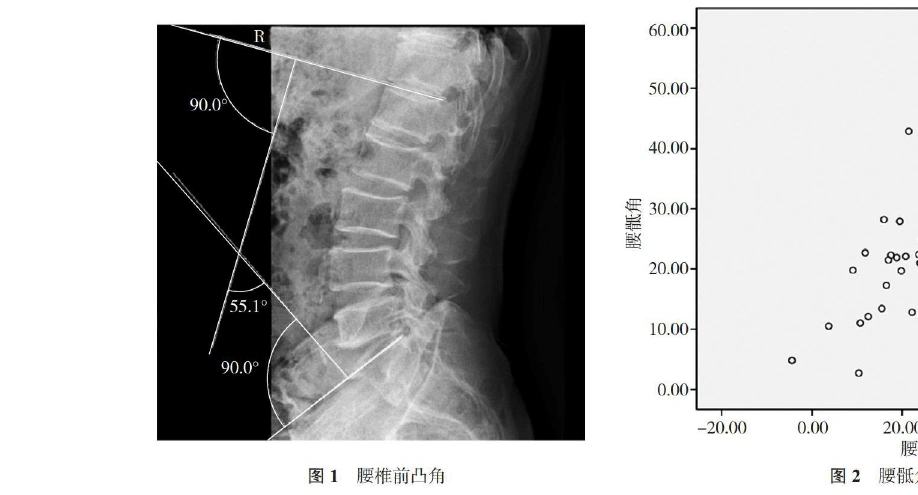

腰骶角和腰椎曲度的相关性研究

腰骶角30-40° 成角:骶骨岬的平面与水平面之间的夹角.

腰骶角是由水平线与s1上终板所成的夹角.参考意义:正常值41.1±7.